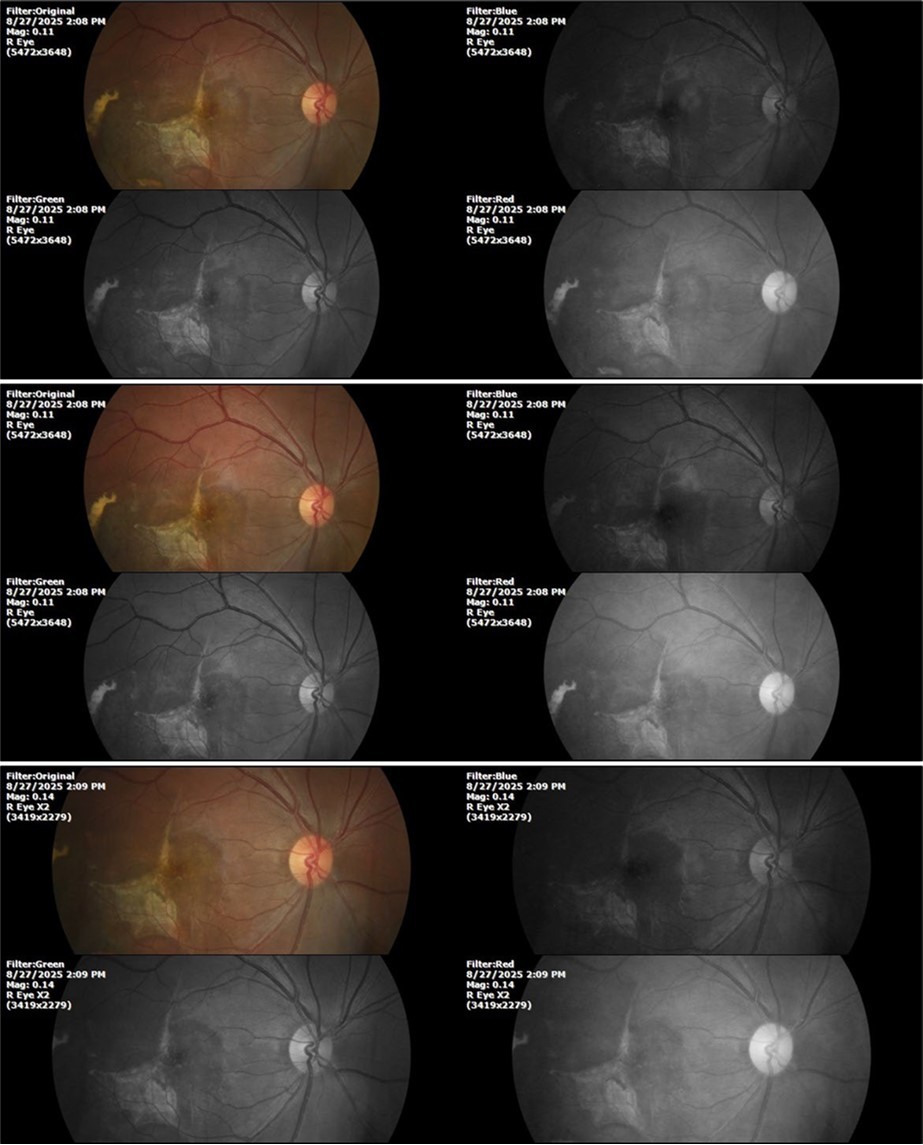

Figure 7.The photograph of the fundus of the right eye shows significant subretinal bleeding, which affects the entire macular area; and some blood is also seen in the vitreous body.

Figure 8.The photograph of the superior temporal region of the retina of the right eye shows the extent of subretinal bleeding as well as retinal edema.

Figure 9.The extent of bleeding, mainly subretinal, is extensive and of significant volume, suggesting choroid rupture in this area.

Figure 10.The location of the bleeding is mainly subretinal, although blood is seen in minimal quantity in the vitreous body.

Figure 27.The three previous photographs of the right fundus show that the whitish mass composed mainly of phantom cells continues to decrease.

Figure 33.The 3 previous photographs show that whitish mass has almost completely disappeared, and to date only a remnant remains on the left side of the photograph. The chorioretinal scar that is now observed corresponds to the area affected by the blunt trauma, which presumably caused rupture of Bruch's membrane. Fortunately, the macular region has recovered almost in its entirety, so the impairment in central vision was minimal.